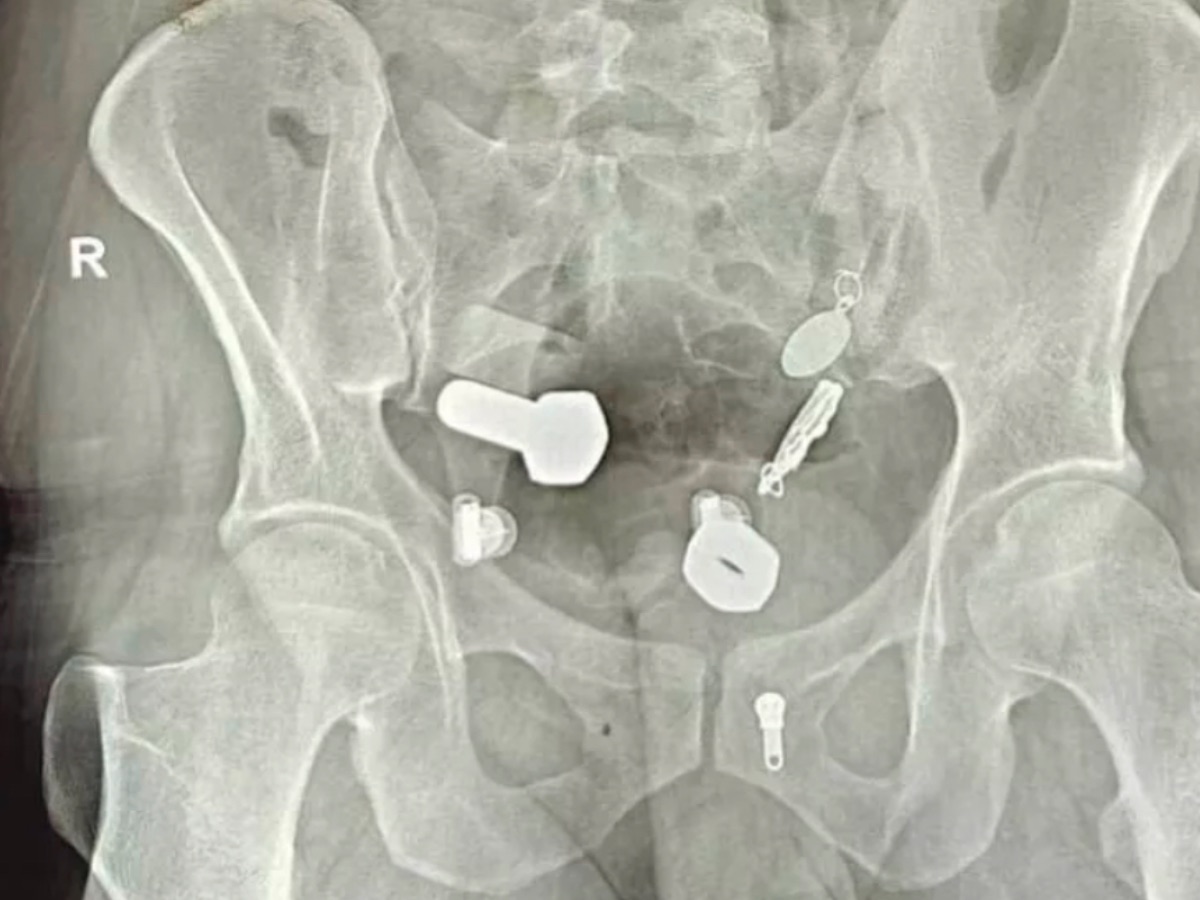

【衝撃X線】腹痛の原因は“腕時計”と“大量のネジ” ― 男性の胃から摘出された「ありえない異物」

2025/10/20 22:30